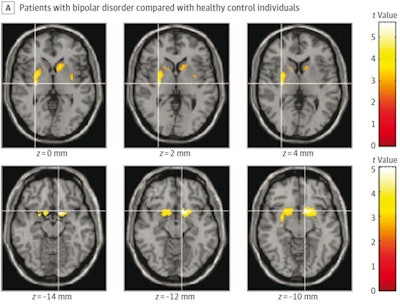

Areas in striatum where carbon-11 d-threo-methylphenidate nondisplaceable binding potentialwas significantly lower. Image courtesy of JAMA Psychiatry.

Results showed that DAT radiotracer binding was significantly lower in patients with bipolar disorder in the right putamen and nucleus accumbens areas of the brain, as well as the left putamen and caudate. The reduction in binding was more extensive and pronounced in patients with current mania, while patients with recently remitted mania had lower binding in the left striatum but not the right, according to the findings.